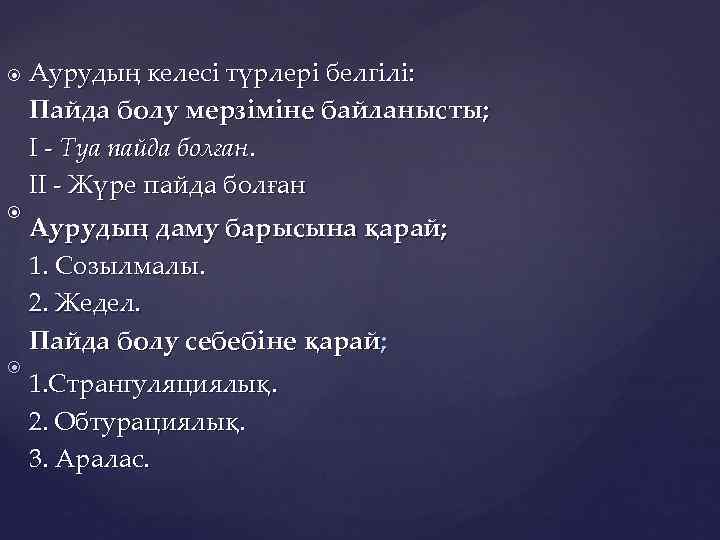

Аурудың келесі түрлері белгілі: Пайда болу мерзіміне байланысты; I - Туа пайда болған. II - Жүре пайда болған Аурудың даму барысына қарай; 1. Созылмалы. 2. Жедел. Пайда болу себебіне қарай; 1. Странгуляциялық. 2. Обтурациялық. 3. Аралас.

Жүре пайда болатындардың себептері: 1. Жарақаттар. 2. Іштің қабынуы (жедел аппендицит, гинекологиялық аурулар). 3. Операциялық жарақаттар (салқындау, құрғау, қан ағу, эвентрация). 4. Химиялық қоздырғыштар (құрғақ антибиотиктер, сульфаниламидтер, тальк). 5. Зат алмасу процессінің бұзылуы (коллагеноз, фибриноген көбеюі және фибринолитиктер кемістігі, ішпердесінің гипоксиясы).

Илеустың жедел, созылмалы және ауыспалы түрлерін бөледі. Жедел илеус - ойда жоқта, бұған дейін дені сау адамда басталып, оның жағдайы тез ауырлайды. Созылмалы илеусқа бәсендеп өсетін ішек ісігі, ал ауыспалы түріне ішектің бұралуы үшыратады. Ішектің толық бітелуі немесе жартылай бітелуі мүмкін. Жартылай бітелуінде нәжіс және газ аздап шығады. Ішек түйілуінің барлық түрлерін механикалық және динамикалық деп екі топқа бөледі. Механикалық деп ішектің бұралуында, қысылуында, бітелуінде, сырттан басылуында байқалатын түрін атайды. Механикалық илеус - странгуляциялық және обтурациялық болып екіге бөлінеді. Странгуляциялық түрінде ішек сыртқы себептен түйіледі. Бұңда ішек ғана емес, оның шажырқайы қысылып қан айналысы бүзылады да қысылған ішектің некрозы басталады.